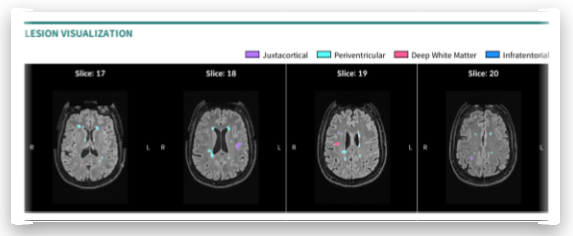

- 주력 사업: 알츠하이머, 치매, 뇌졸중 등 신경계 질환 진단/치료 보조 솔루션 개발

- 솔루션 경쟁력: AI 기반 MRI/CT 영상 자동 분석, 미세 변화 탐지, 임상시험 보조 등 전주기 대응

- 시장성: 알츠하이머 치료제 도입으로 MRI 등 영상 촬영량 급증 전망(투약 전·후, 치료과정마다 촬영 필요)